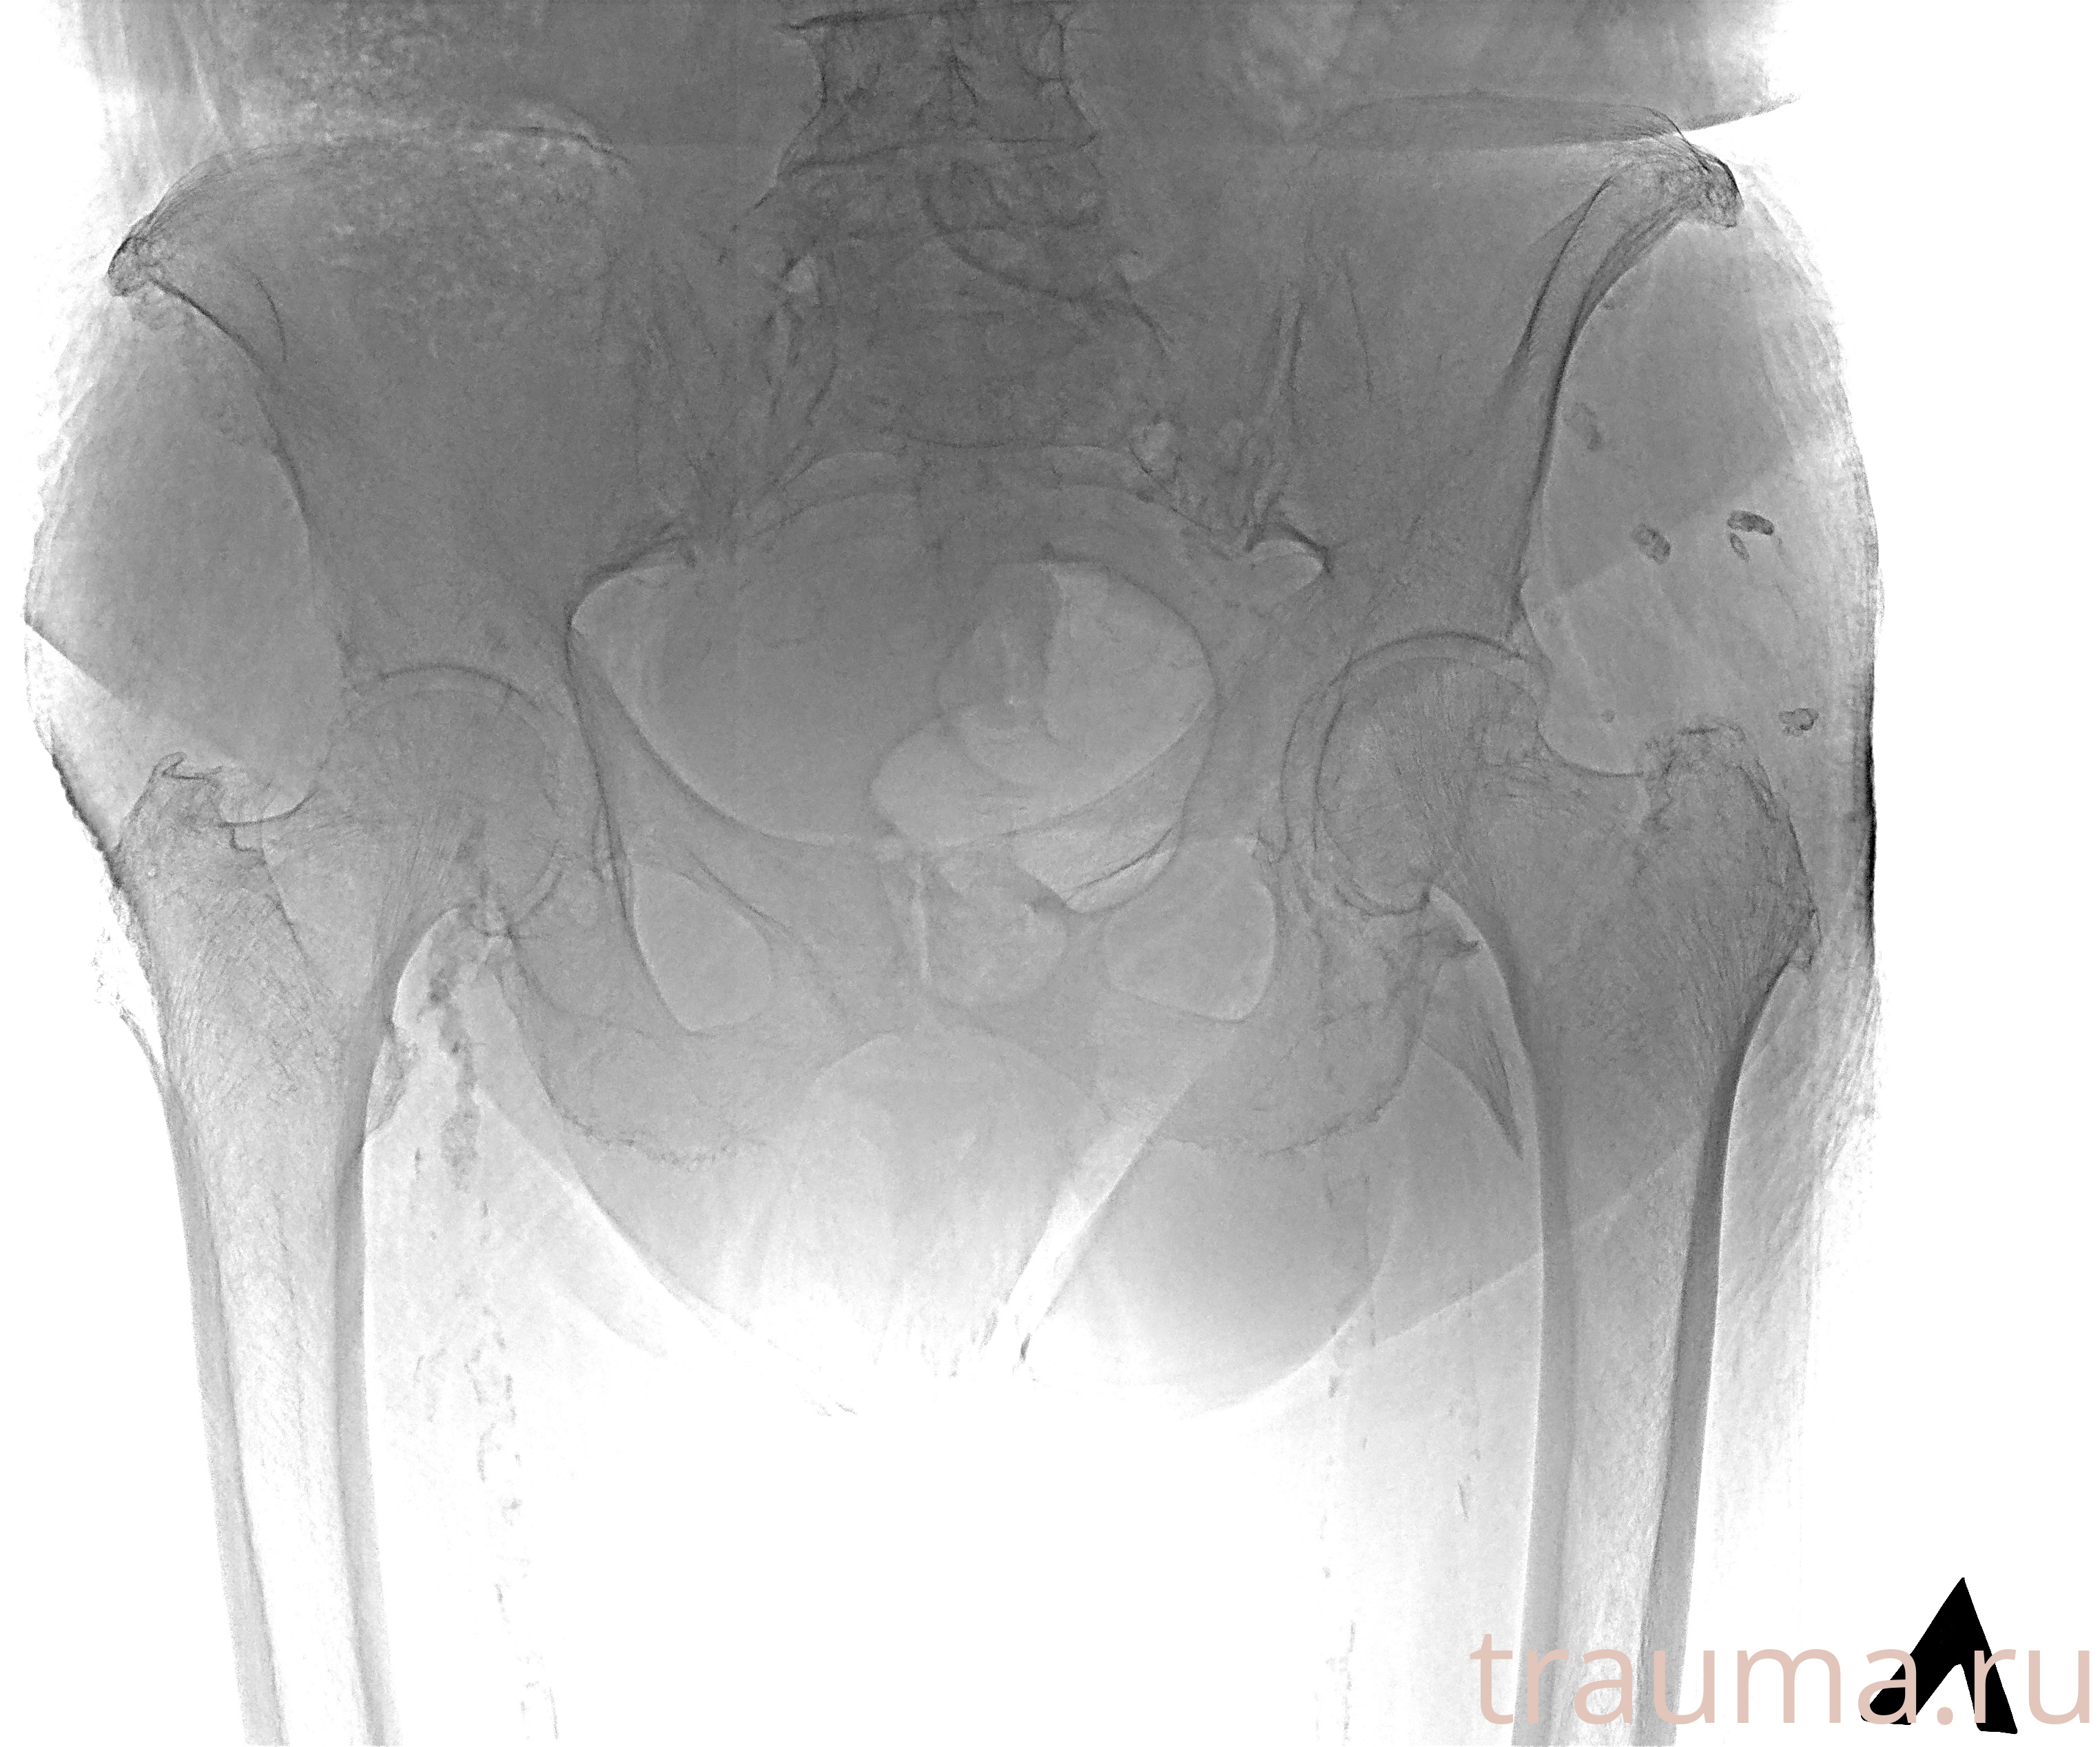

Рентгенограммы

Рентген на дому: по вашему адресу приезжает врач-рентгенолог, травматолог-ортопед с мобильным рентгеновским аппаратом, проводит диагностику травмы или заболевания, делает необходимые рентгенограммы, дает рекомендации по дальнейшему лечению. Получить качественные снимки в домашних условиях возможно благодаря уникальной методике, разработанной МосРентген Центром для института  Склифосовского

Яркость: 1   Контраст: 1   Инвертировать: 0 Увеличение: 1

Перетаскивайте мышь вверх/вниз для контраста, влево/право для яркости. Прокрутка колесом изменяет масштаб. Нажмите Сбросить для возврата к исходному изображению. При увеличении держите мышь в той области, которую хотите рассмотреть.